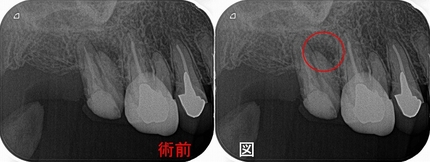

3本神経管はあるのですが、近心頬側根が手付かずで根尖病変が見られます。

手前の第一大臼歯も近心頬側根は手付かずですが、病変はありません。(病変がないのでわざわざ治療は私はしません)